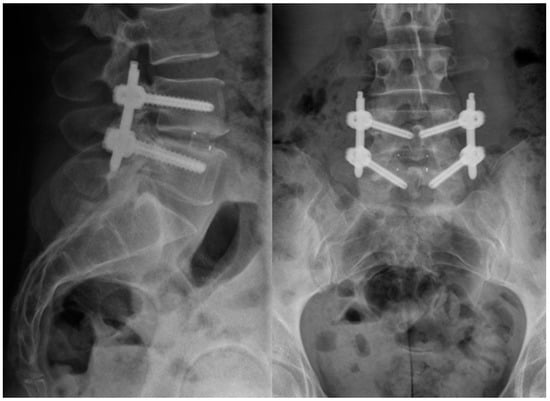

4.2. Implant

4.3. Surgical Technique